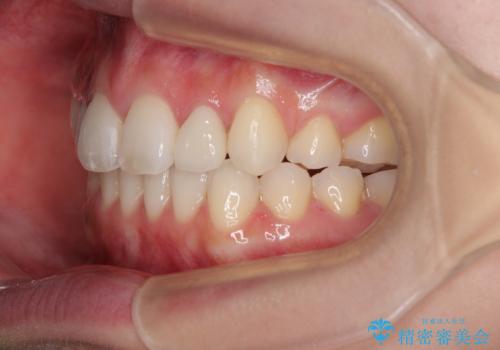

しかしながら、左右ともに側切歯が矮小歯であるため、矯正治療で矮小歯前後にスペースを作り、矯正治療後にオールセラミッククラウンにて補綴治療を行うこととしました。

治療途中で地元へ転居され、飛行機での通院となったため、治療期間が長くなりましたが、自然で整った口元に仕上げることができました。